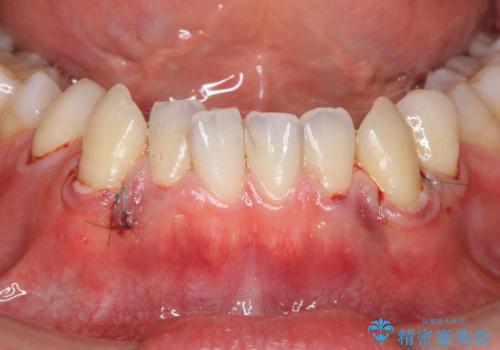

歯茎の下がりが気になる 歯肉移植でさがりにくくする

- 下の犬歯の歯茎の下がりを気にされていました。

矯正治療予定であったので、矯正治療前に歯茎の移植を行い、さらに退縮するのを防ぎました。

下がったのを元に戻すことは必ずしもできないですが、厚みを増やして下がりにくくすることはできます。今回左下の犬歯は特に、しっかり下がったのも元に戻すことができ、大変うまくいきました。